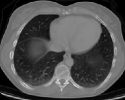

4.1.5 Chest CT

Chest CT scans play a relevant role in diagnosing a wide range of thoracic diseases, from infections to malignancies. By analyzing those scans, it is possible to detect diseases in the chest region, including pneumonia and cancer. The selected chest CT dataset 555https://www.kaggle.com/datasets/mohamedhanyyy/chest-ctscan-images contains 967 images across normal and three cancer types: adenocarcinoma, large-cell carcinoma, and squamous-cell carcinoma. Figure 6 provides a visual representation of the four highlighted classes.